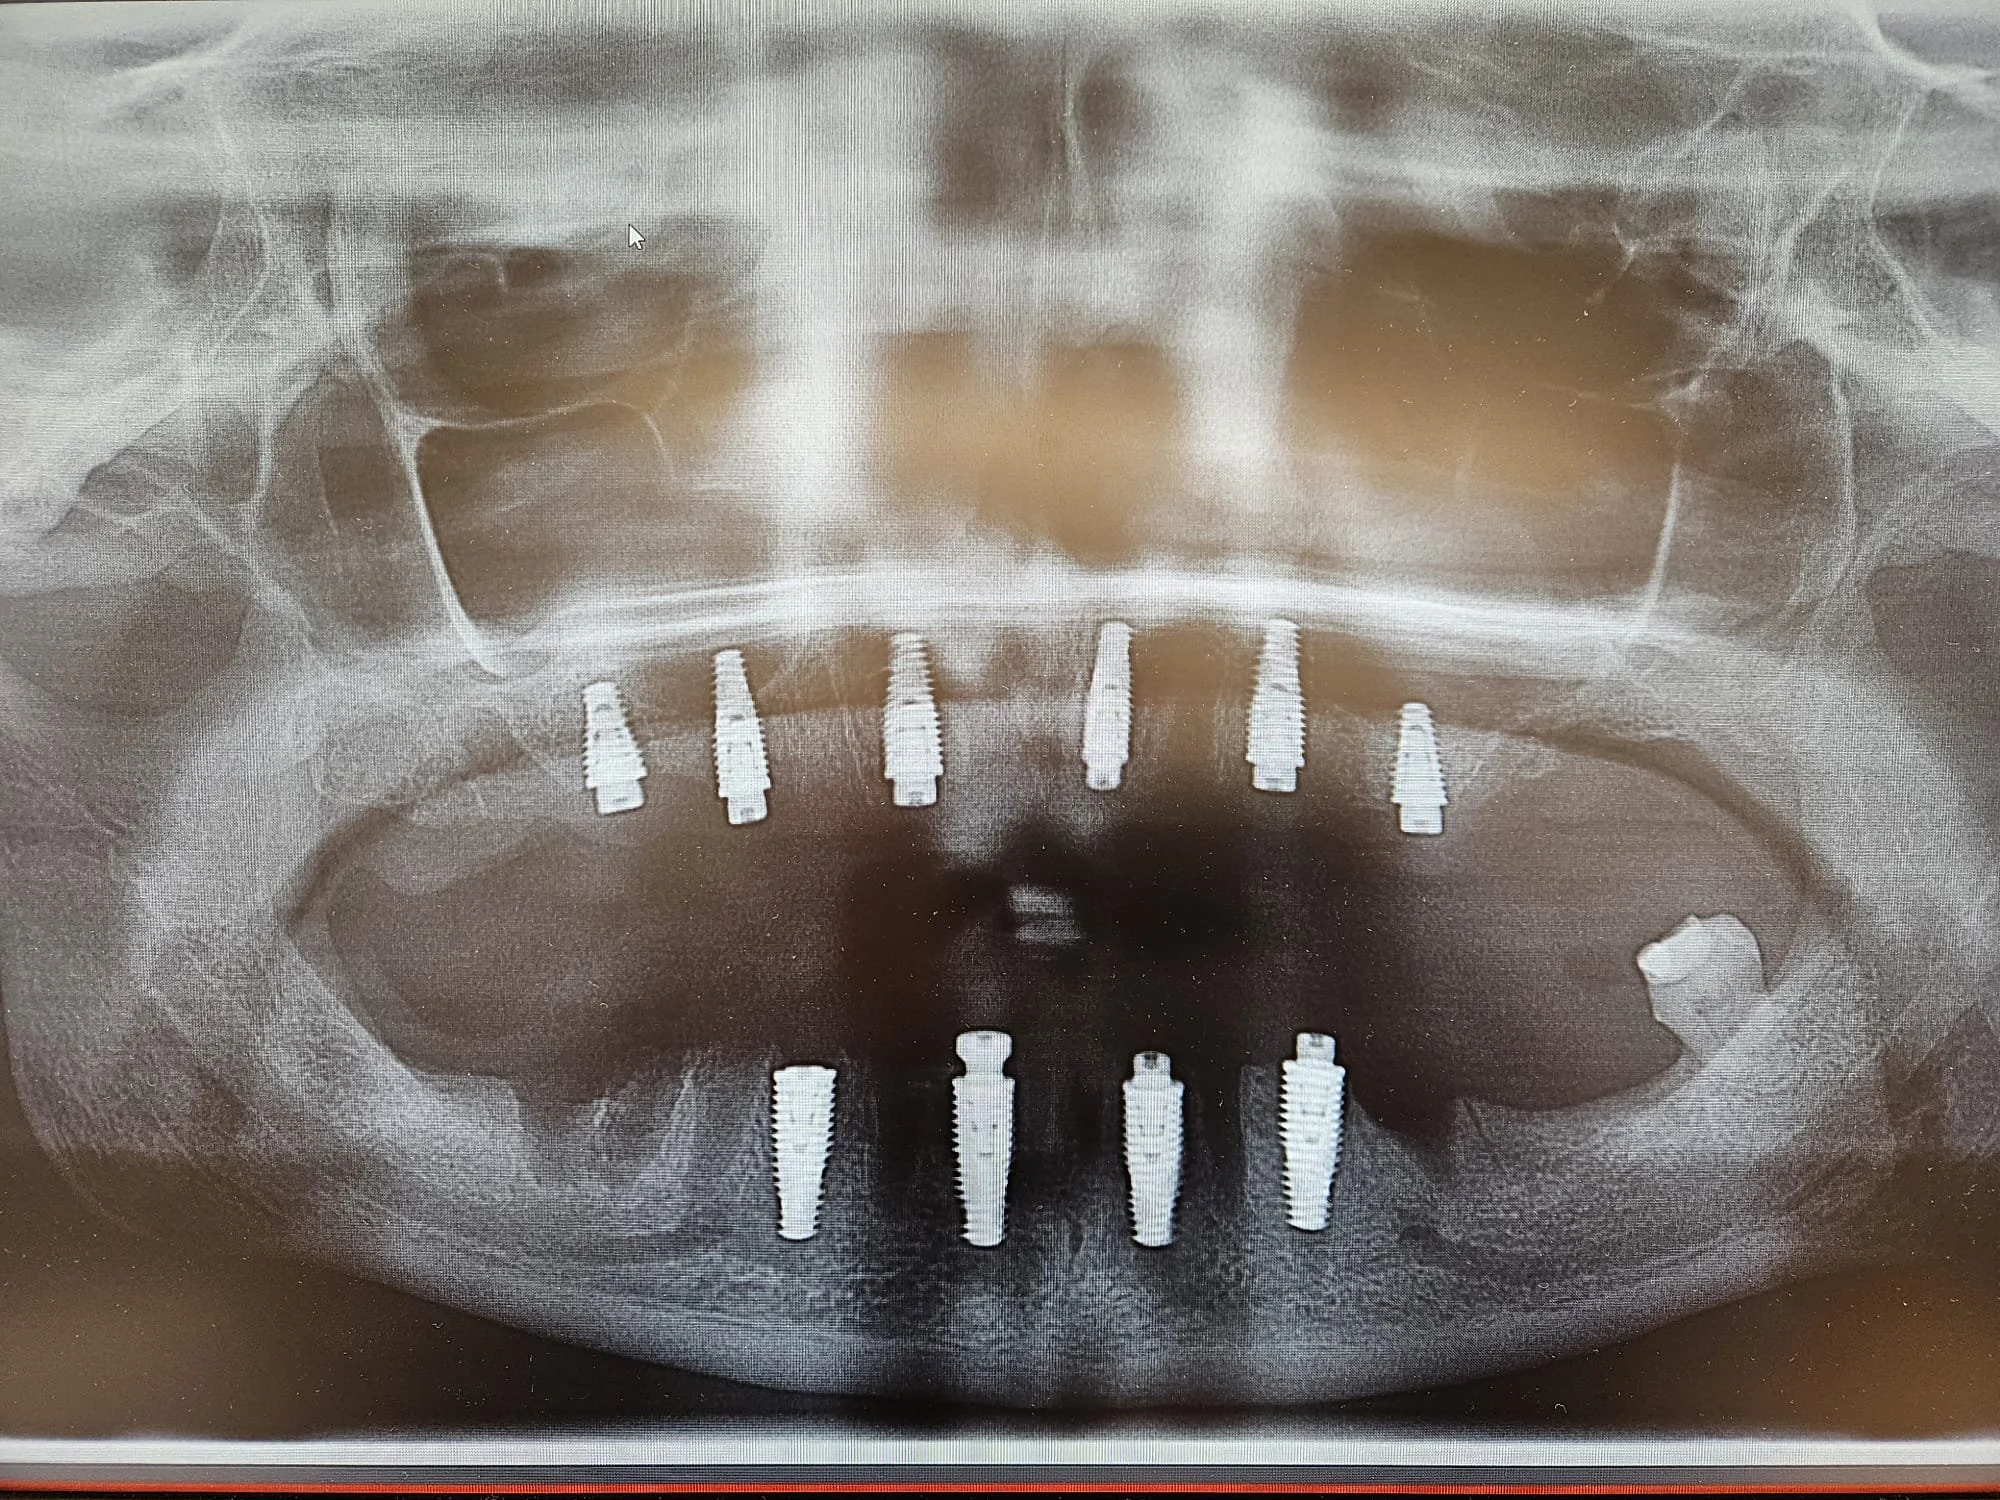

1- Planification chirurgicale et prosthodontique d’un cas de prothèses sur implants fixes maxillaire et mandibulaire

1- Extraction bouche complète maxillaire et mandibulaire ainsi que la pose d'implants simultanément en vue de prothèses complètes implanto-portées fixes, par Dr Farid Amer-Ouali

2- Mise en charge immédiate de prothèses complètes fixes temporaires maxillaire et mandibulaire, par Dr Bilal El-Masri

3- Extraction complète maxillaire ainsi que la pose d'implants simultanément en vue de prothèse complète amovible implanto-portée, par Dr Farid Amer-Ouali